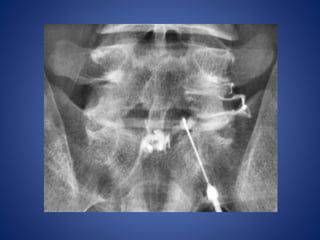

Facet Joint Capacity

Right L5–S1 facet injection with

guided fluoroscopy

Right L5–S1 facetinjection with guided fluoroscopy